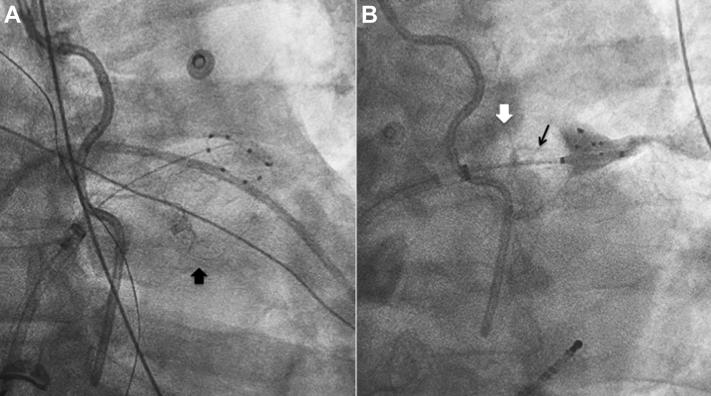

Cryoballoon pulmonary vein isolation and voltage mapping for symptomatic atrial fibrillation 9 months after Watchman device implantation.